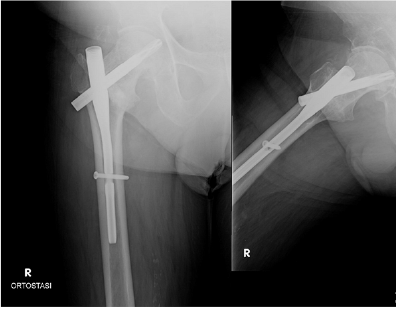

The patient was a 68 years old male, who had a car accident (Table 1). When he was admitted to the hospital, X-ray examination revealed a fracture of the surgical neck of left humerus and a fracture of the right femoral neck. He was treated with an intramedullary nailing of the femur (Proximal Femoral Nail Antirotation - PFNA system by ©DePuy Synthes) (Figure 1). The humerus fracture was managed conservatively with a shoulder immobilization for the first two weeks. The patient had an uneventful postoperative period, and he began immediately postoperative rehabilitation without weight bearing for the first two weeks. He continued his rehabilitation program in the following months, after hospital discharge, in a physiotherapy centre near his home. He placed on him from the third week, and two weeks later he has recovered to walk by himself, with the help of two crutches. At 6 months of follow-up, the Physicians (M.P., D.L.) noted a delayed healing of the fractures on X-ray (Figure 2), despite the good clinical condition of the patient, in fact he had no pain, and he was able to walk by himself without crutches or a limp. In addition, the patient missed the one-year follow-up due to pandemic emergency in March 2020. Two months after, he developed groin pain of the right hip and it was treated with a phone consultation by his general practitioner for a sciatic problem. Because of the persistent pain he called his surgeon who prescribed a new X-ray that revealed a superomedial migration of the proximal femoral blade, a phenomenon called cutin [12] (Figures 3 & 4). For this reason, the patient underwent a primary total hip arthroplasty with stem revision (©Lima Corporate) in October 2020 (Figure 5).

Figure 3: X-ray fourteen months after surgery and cut-in phenomenon.